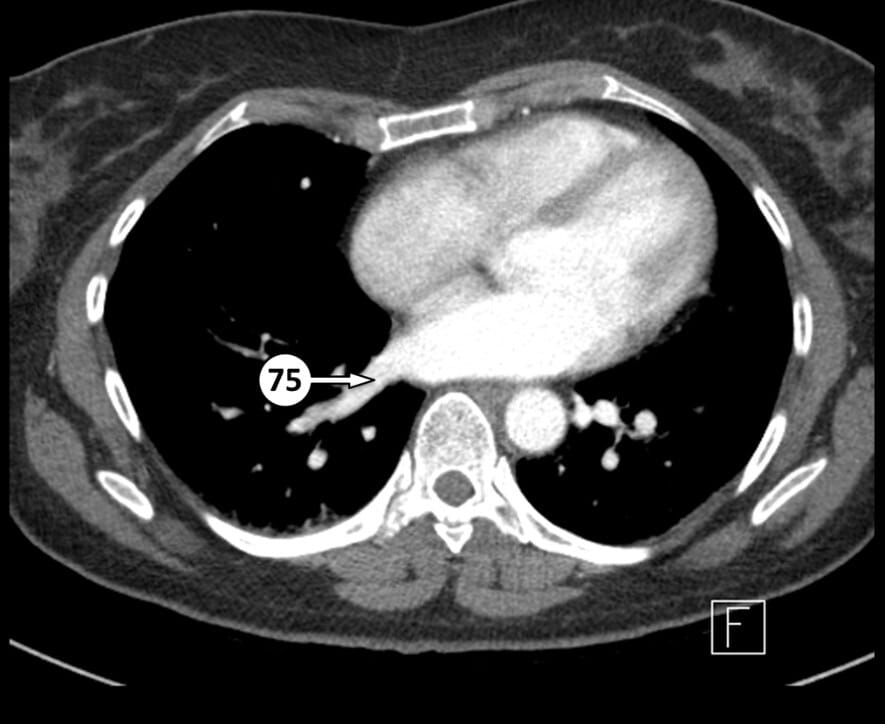

75. right inferior pulmonary vein